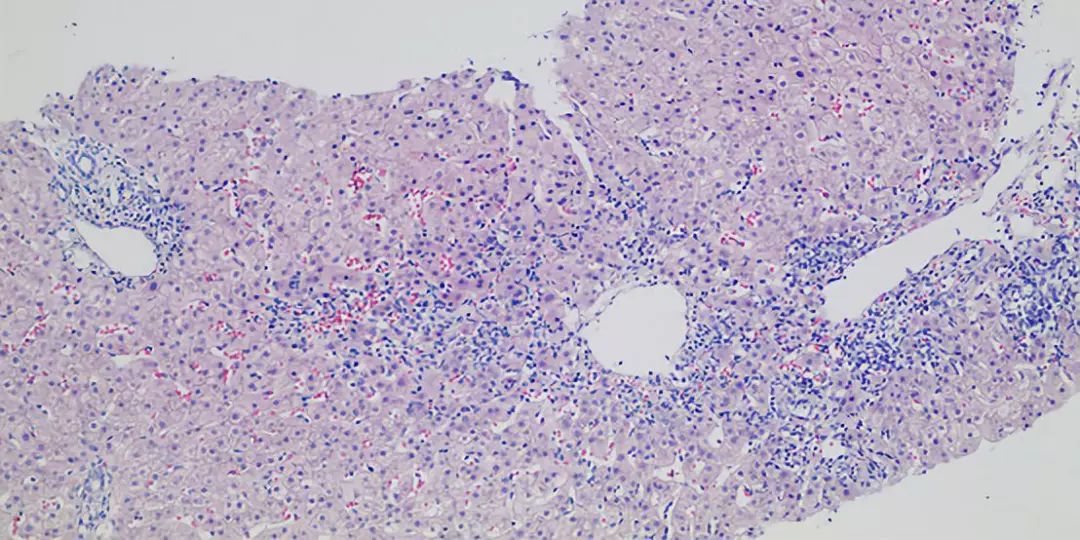

正常界面

正常肝小叶

①肝细胞变性:细胞水肿、嗜酸变性;②肝细胞坏死:1.溶解性坏死:点状坏死、碎片状坏死、桥接坏死、大片坏死;2.凋亡:嗜酸小体;③炎细胞浸润:淋巴细胞、浆细胞、中性粒细胞、嗜酸性粒细胞等;④再生:肝细胞再生、间质反应性增生(枯否细胞、成纤维细胞)、小胆管增生;⑥纤维化

主要累及肝细胞的炎症:病毒性肝炎、药物性肝炎、非酒精性脂肪肝炎、酒精性肝炎、自身免疫性肝炎。累及胆管的炎症主要包括原发性胆汁性胆管炎、原发性硬化性胆管炎…